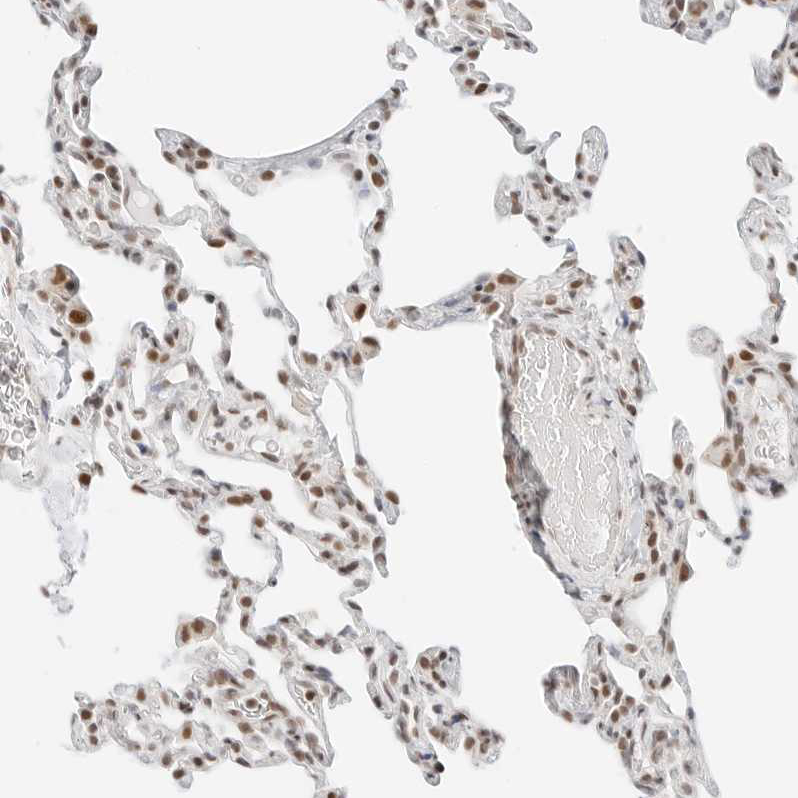

Immunohistochemical staining of human lymph node shows moderate nuclear positivity in germinal center cells.